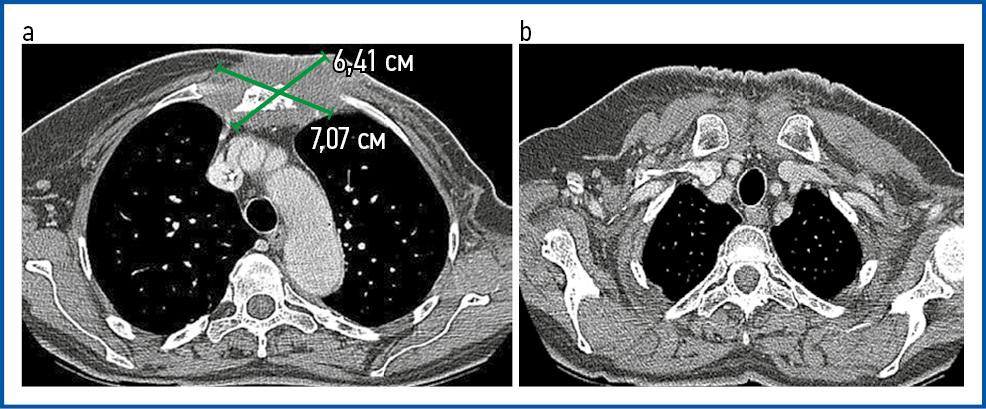

Положительный эффект зафиксирован к моменту окончания ЛТ в виде частичной регрессии первичной опухоли более 50% и отсутствия эпизодов кровотечения (рис. 4, 5, a).

Рис. 4. Картина КТ грудной клетки после ЛТ. Размеры опухолевых узлов обозначены зелеными линиями: a – вид грудной стенки на уровне ThV позвонка; b – вид грудной стенки на уровне ThIII позвонка.

Fig. 4. CT scan of the chest after RT. The dimensions of the tumor nodes are indicated by green lines: a – view of the chest wall at the level of the ThV vertebra; b – view of the chest wall at the level of the ThIII vertebra.

Учитывая выраженный положительный эффект от ранее проведенной ЛТ, появление ограниченного числа новых очагов, с 29.11.2022 по 05.12.2022 проведен паллиативный курс конформной дистанционной ЛТ на ускорителе электронов Elekta Infinity. В область облучения вошел опухолевый конгломерат правой аксиллярной области, РОД – 6 Гр ежедневно 5 раз в неделю, СОД – 30 Гр (EDQ2 – 54 иГр, при α/β=3). Дозное распределение в зоне мишени отражено на рис. 7.

Рис. 7. Дозное распределение в области облучения. Красной линией указана мишень GTV – лимфатический узел в правой аксиллярной области; зеленая линия – СTV – с отступом от GTV на 10 мм; желтая линия – PTV – с отступом краниокаудально 12 мм, 10 мм во всех остальных направлениях от CTV с учетом границ критических структур.

Fig. 7. Dose distribution in the irradiation area. The red line indicates the GTV target – the lymph node in the right axillary region; the green line indicates CTV at a distance of 10 mm from GTV; and the yellow line indicates PTV with a craniocaudal distance of 12 mm and 10 mm in all other directions from CTV, taking into account the boundaries of critical structures.

Через 3 мес после завершения ЛТ зафиксирована выраженная положительная динамика в виде уменьшения размера метастатически измененного аксиллярного лимфатического узла справа до 6 мм (ранее 20 мм), с накоплением 18F-ФДГ SUVmax 1,86 (ранее 31,29).